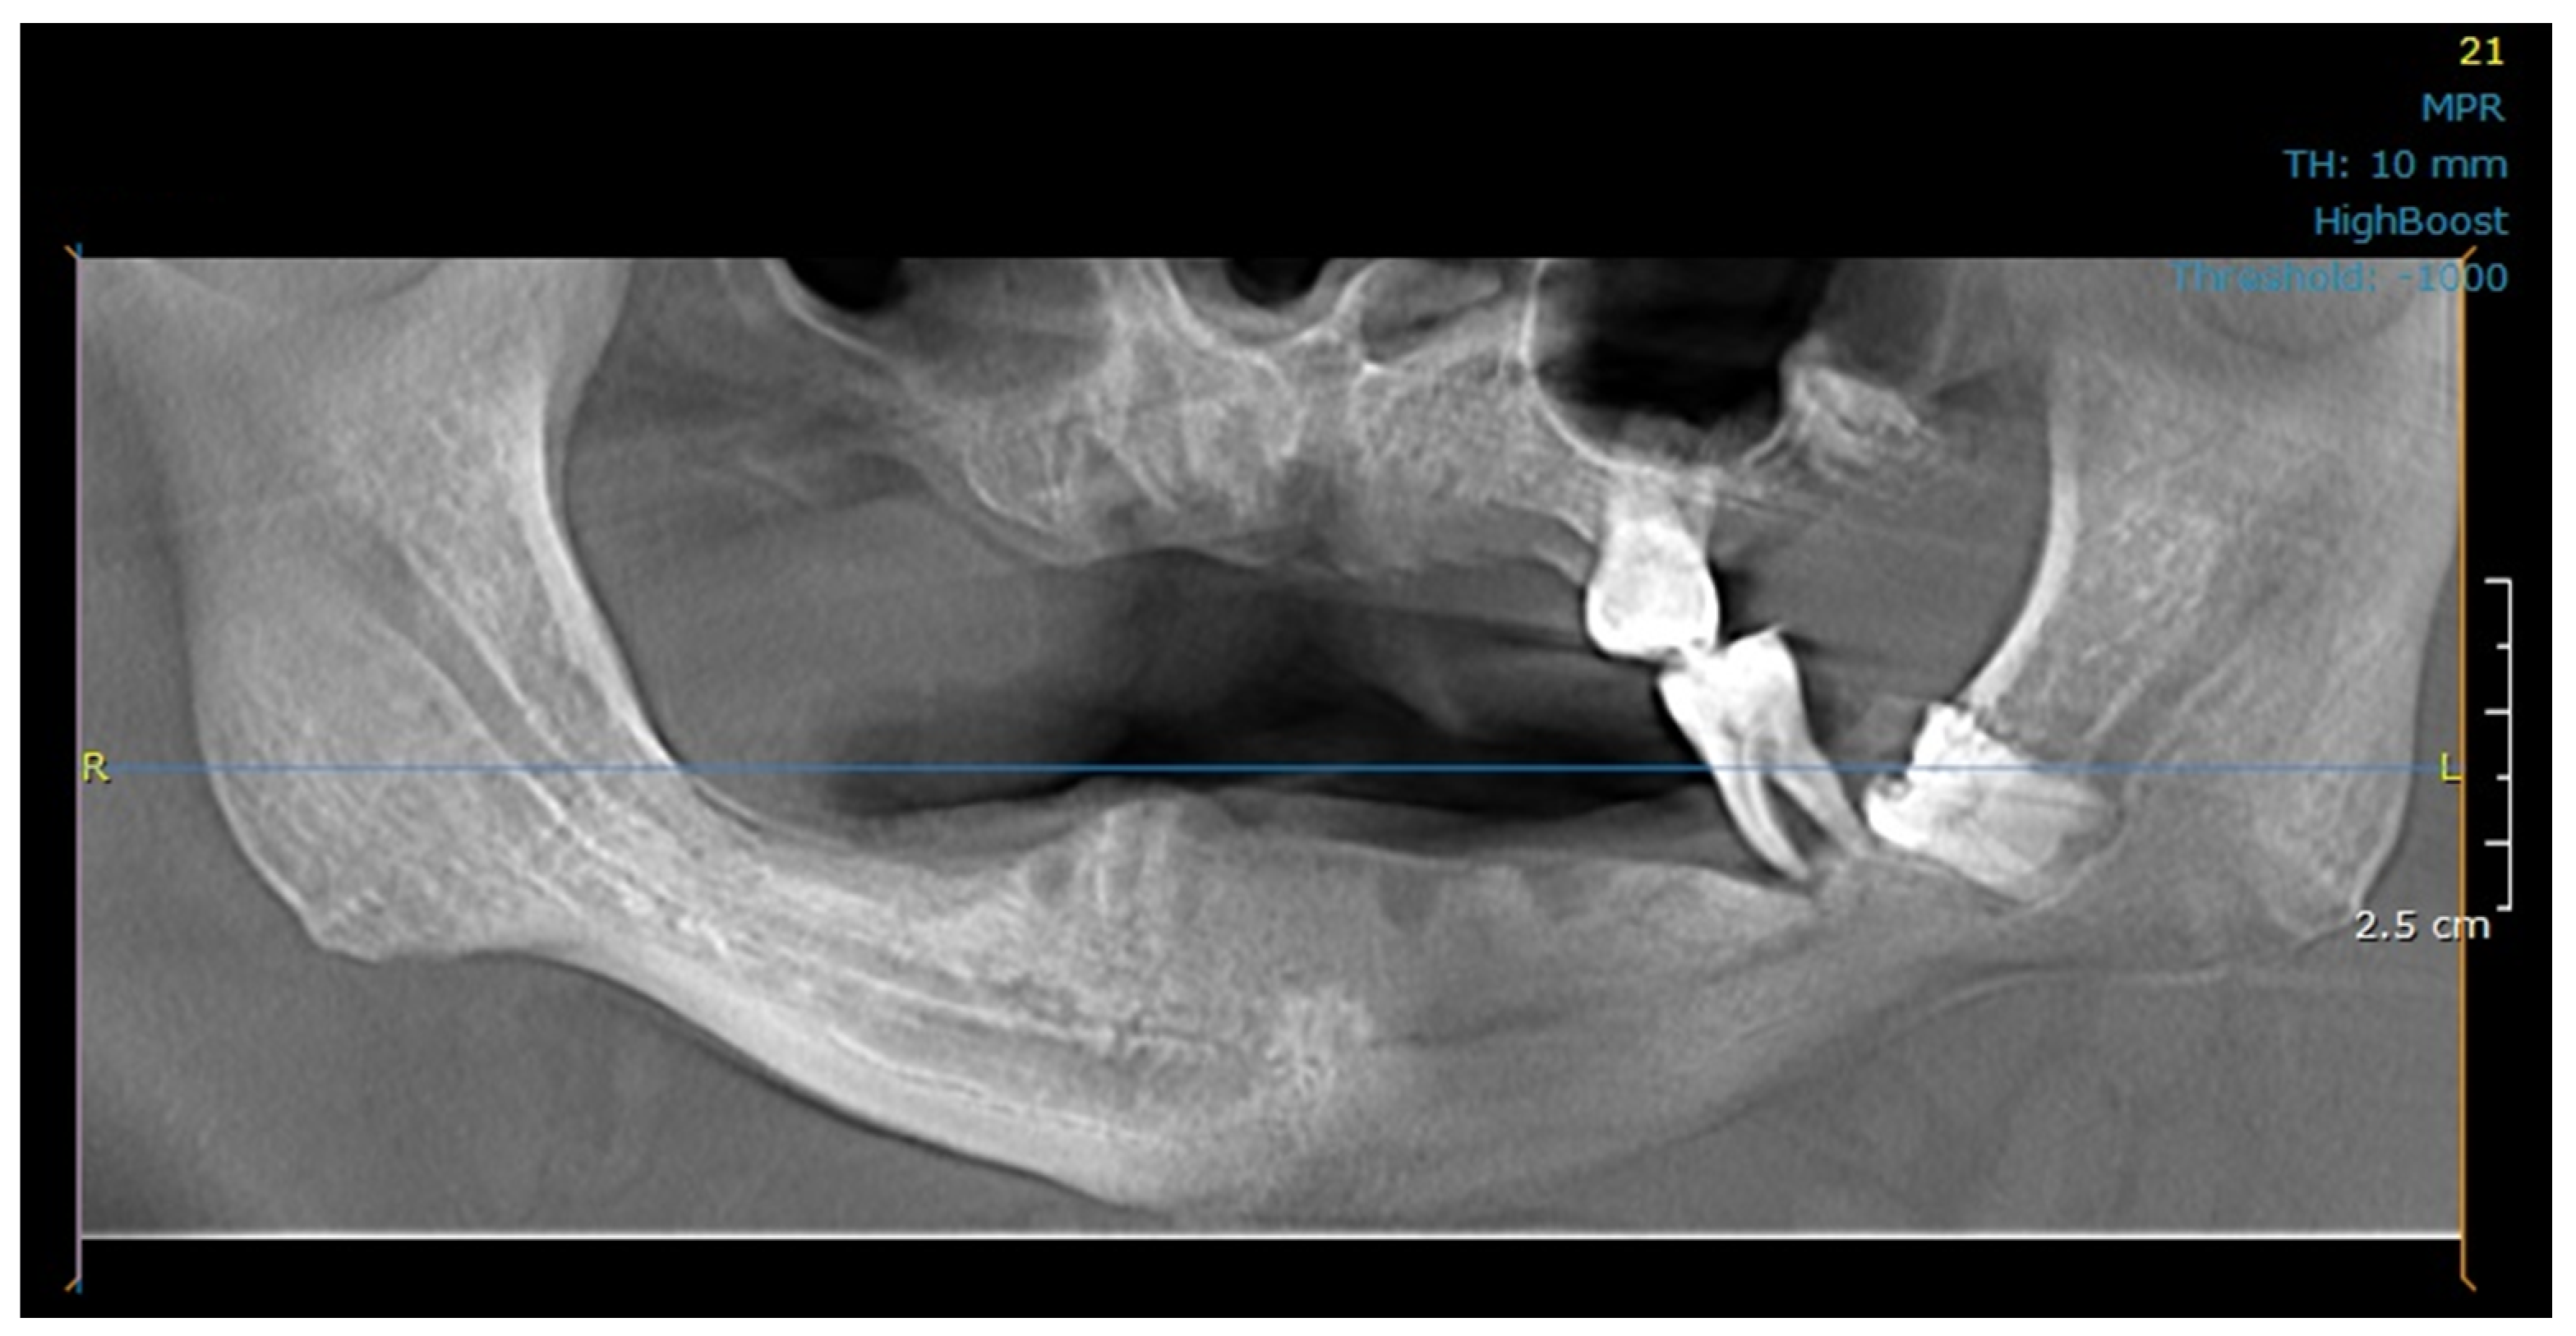

2.1. Study Design, Patient Treatment Characteristics

2.3. Modeling